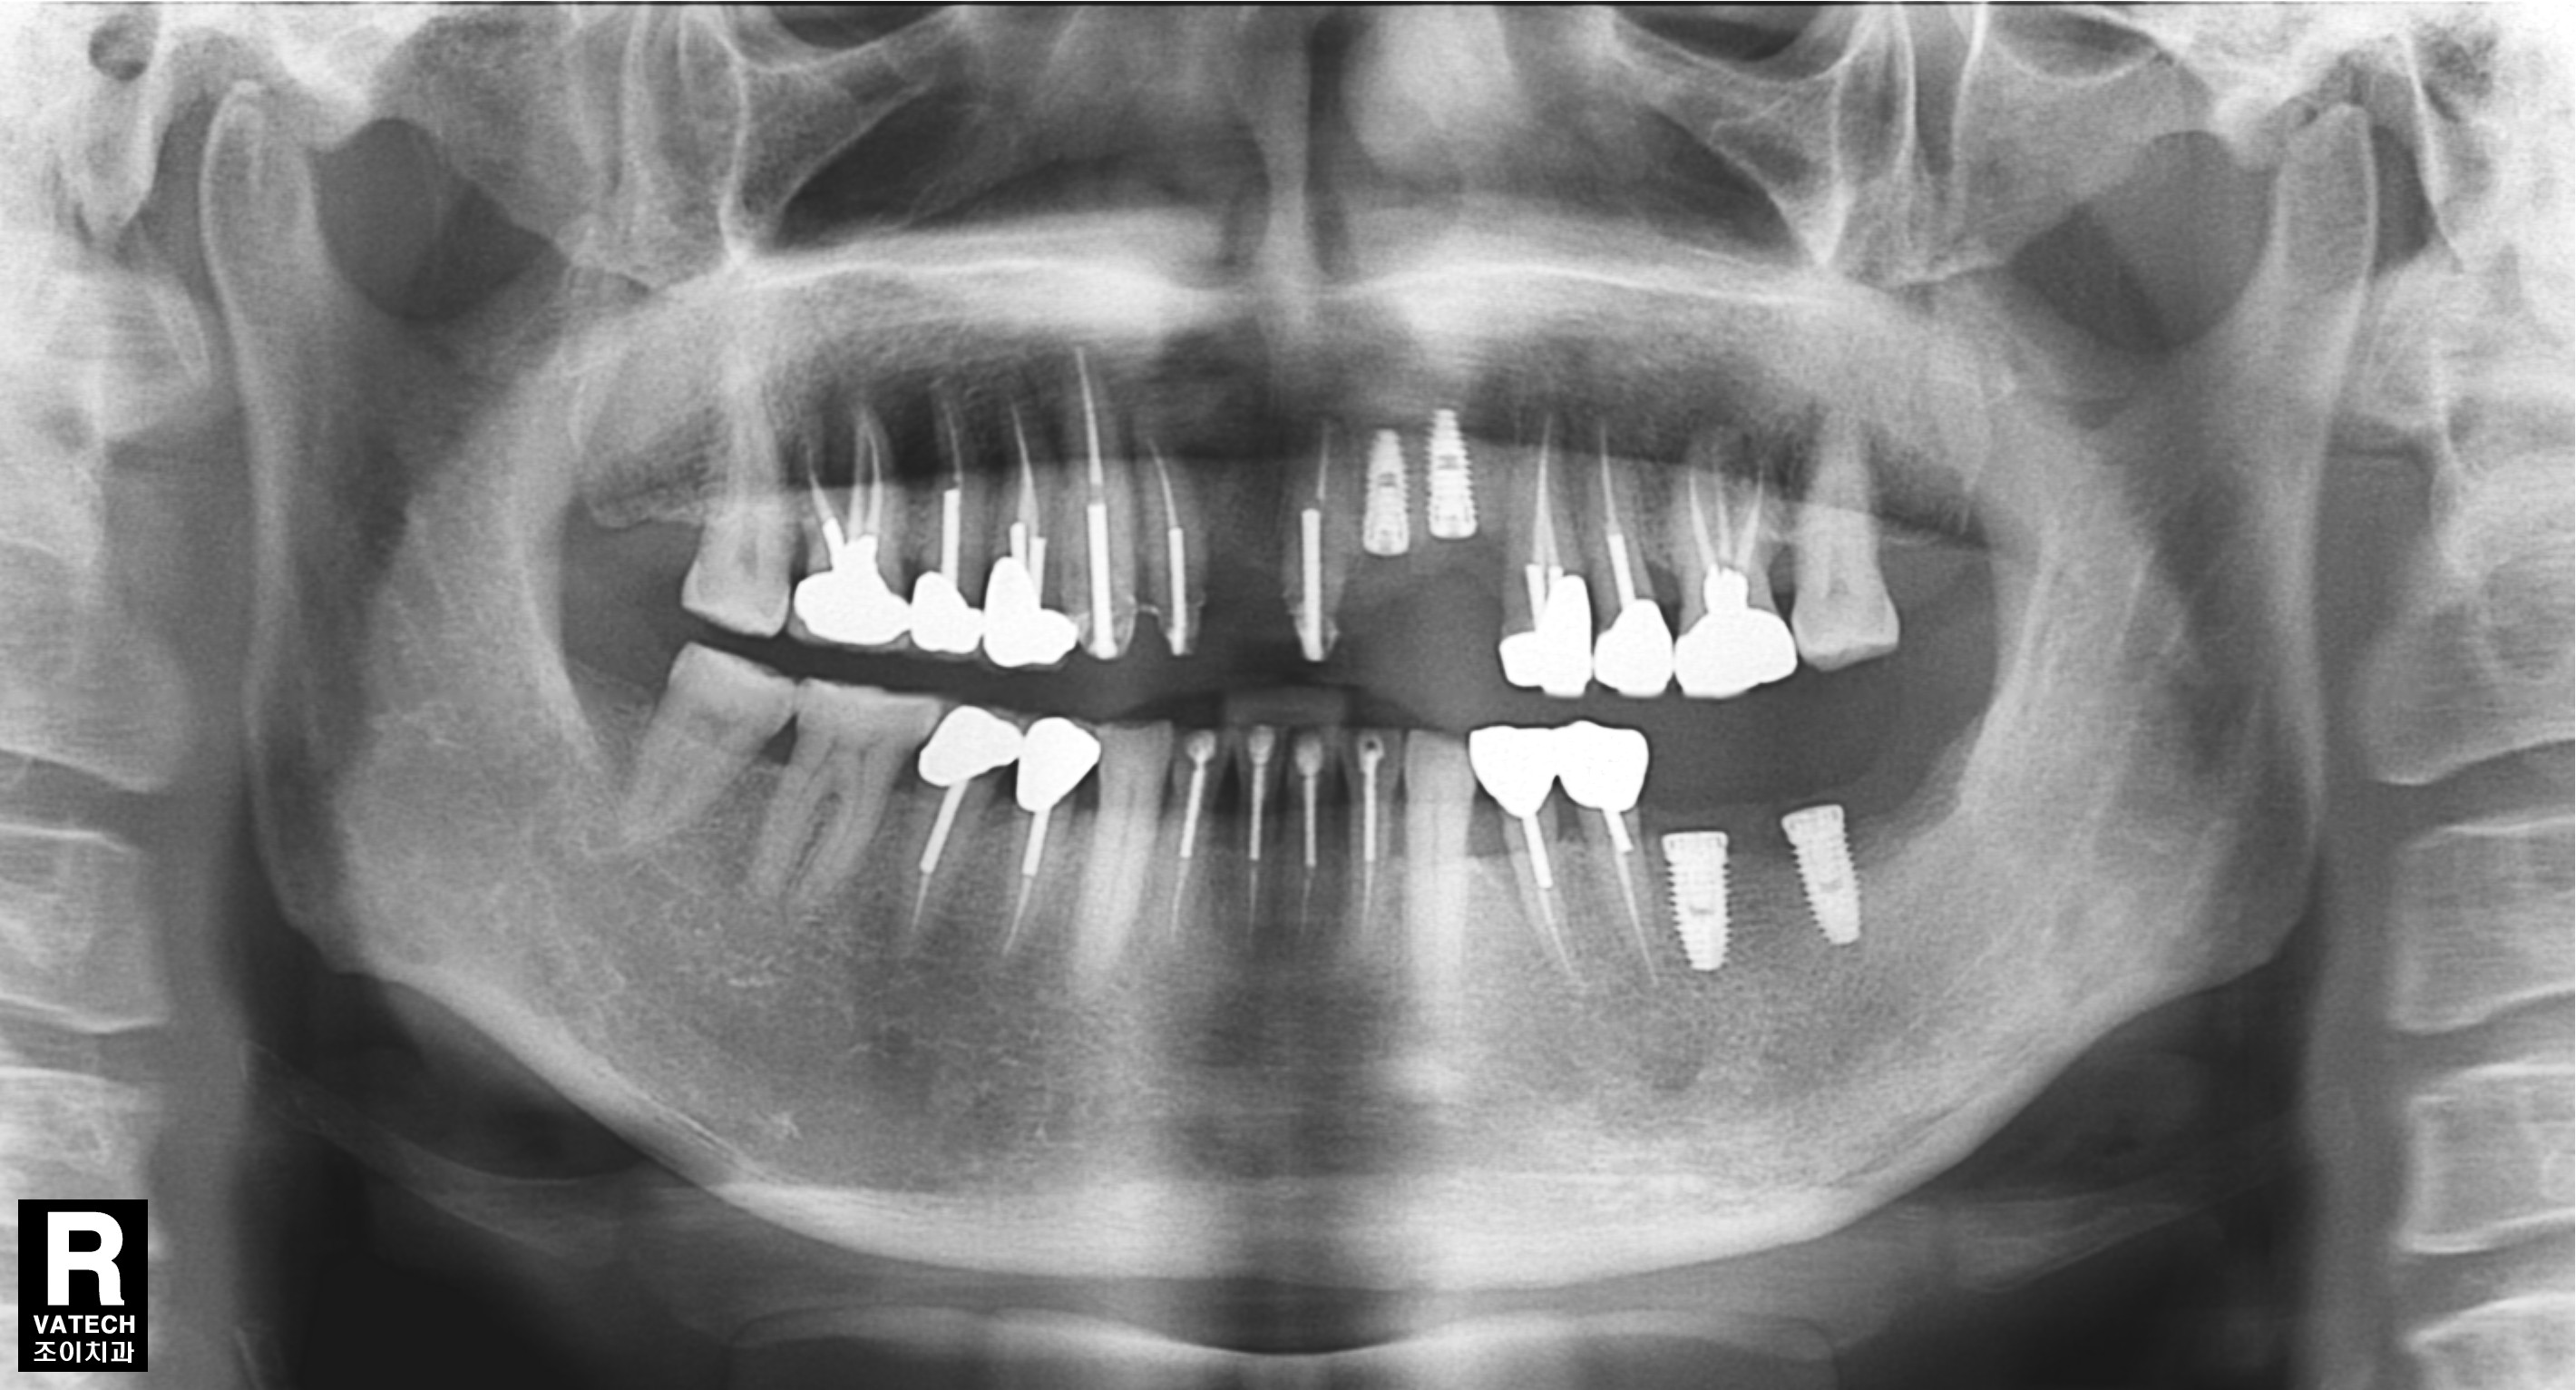

[임플란트] 제목 : 임플란트와 보철치료의 조화

오래된 보철의 파손으로 치료한 사례입니다.